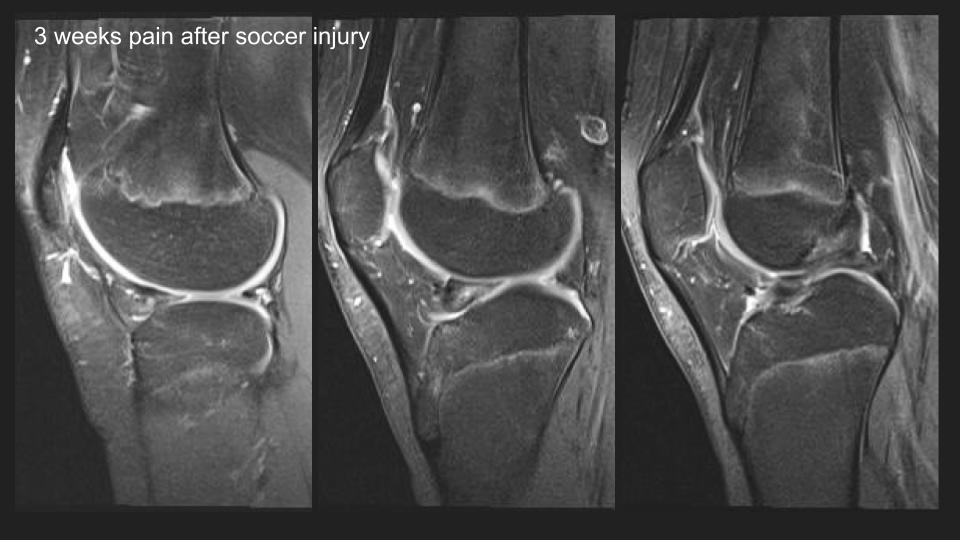

12M 3 weeks after soccer injury

There is an anteriorly flipped bucket-handle type tear of a discoid lateral meniscus, which is not so interesting, until you see the prior MRI 16 months ago. At that time it appears that there was medial displacement of the posterior portion of the discoid LM, with thick irregular linear structures adjacent to the posterior horn region that I think were torn popliteomeniscal fascicles. Perhaps that predisposed to the current injury. The alternative possilbility is that this is a hypermobile discoid lateral meniscus, perhaps a Wrisberg variant. What do you think? Reference article.